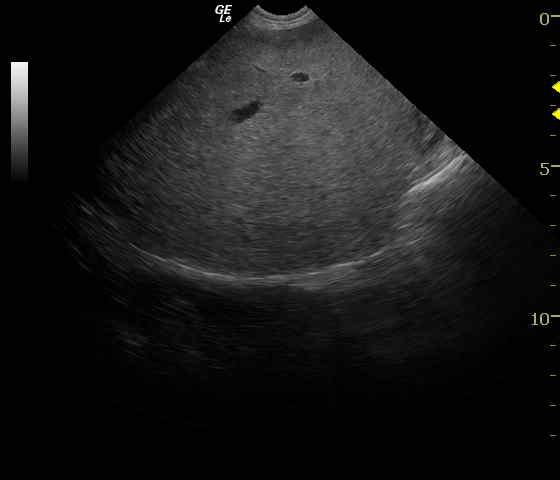

The small intestine presented a shadowing luminal structure consistent with foreign body. Some bunching of small intestine was present with considerable artifact (Video 1). Gastric stasis was present but minimal. The remainder of the intestinal tract appeared edematous most consistent with enteritis. Hyper-peristaltic and dilated small intestine is present with concurrent empty small intestine consistent with an obstructive pattern (Video 2). The spleen was inverted in position and rotated consistent with partial splenic torsion. Vascular congestion was evident (Video 3).

Exploratory surgery revealed a thickened, irregular spleen with no evidence of rupture. Splenectomy was performed. Histopathology of the spleen revealed extensive areas of hemorrhage and hematoma formation, hemosiderosis, extramedullary hematopoiesis, and siderotic capsular plaques. In the intestines, a string foreign body was found and removed, with concurrent resection and anastomosis of small intestine. Histopathology revealed acute on chronic inflammatory bowel.